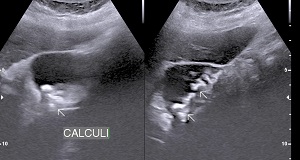

• Choleydocholithiasis (Calculus/ Calculi in Biliary tree): Passage of calculus/caculli in common bile duct leads to biliary colic, nousea, vomitting.

• Surgical jaundice and pancreatitis are complication.